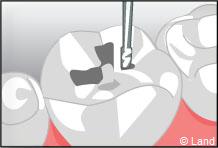

Un inlay reconstitue l’anatomie dentaire en comblant une cavité taillée dans la dent.

L’onlay intéresse aussi la surface occlusale (masticatoire) de la dent.

Inconvénient mineur : sauf dans certains cabinets équipés en CFAO (Conception et Fabrication Assistées par Ordinateur), cette technique nécessite 2 séances de soins, car une étape de laboratoire s’intercale entre la réalisation de la cavité et la pose et le scellement des inlays onlays réalisés en métal, en résine composite ou en céramique.